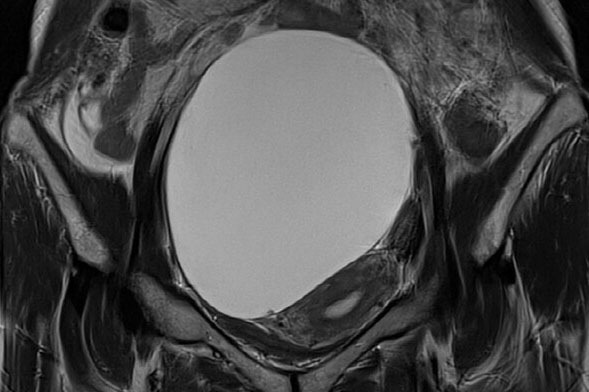

난소낭종, 종류별 치료 전략이 중요한 이유